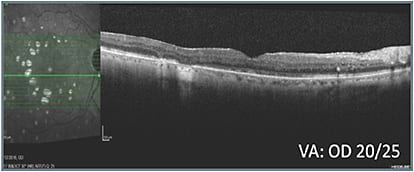

A series of treatments, during the course of which vision ranged from 20/50 to 20/25, failed to resolve the macular edema (B). With vision in the right eye consistently worse than in the left eye and worsening, and the patient experiencing hardship remaining away from home for treatment, an alternative class of therapy was initiated and led to improved retinal anatomy (C, D, & E). Intraocular pressure (IOP) increased to 25 mm Hg and was observed without treatment. When pressure increased to 28 mm Hg, the patient was started on a topical IOP-lowering drop, which lowered the pressure to 19 mm Hg. The right eye has remained fluid free on the alternative class of therapy and a single IOP-lowering agent.